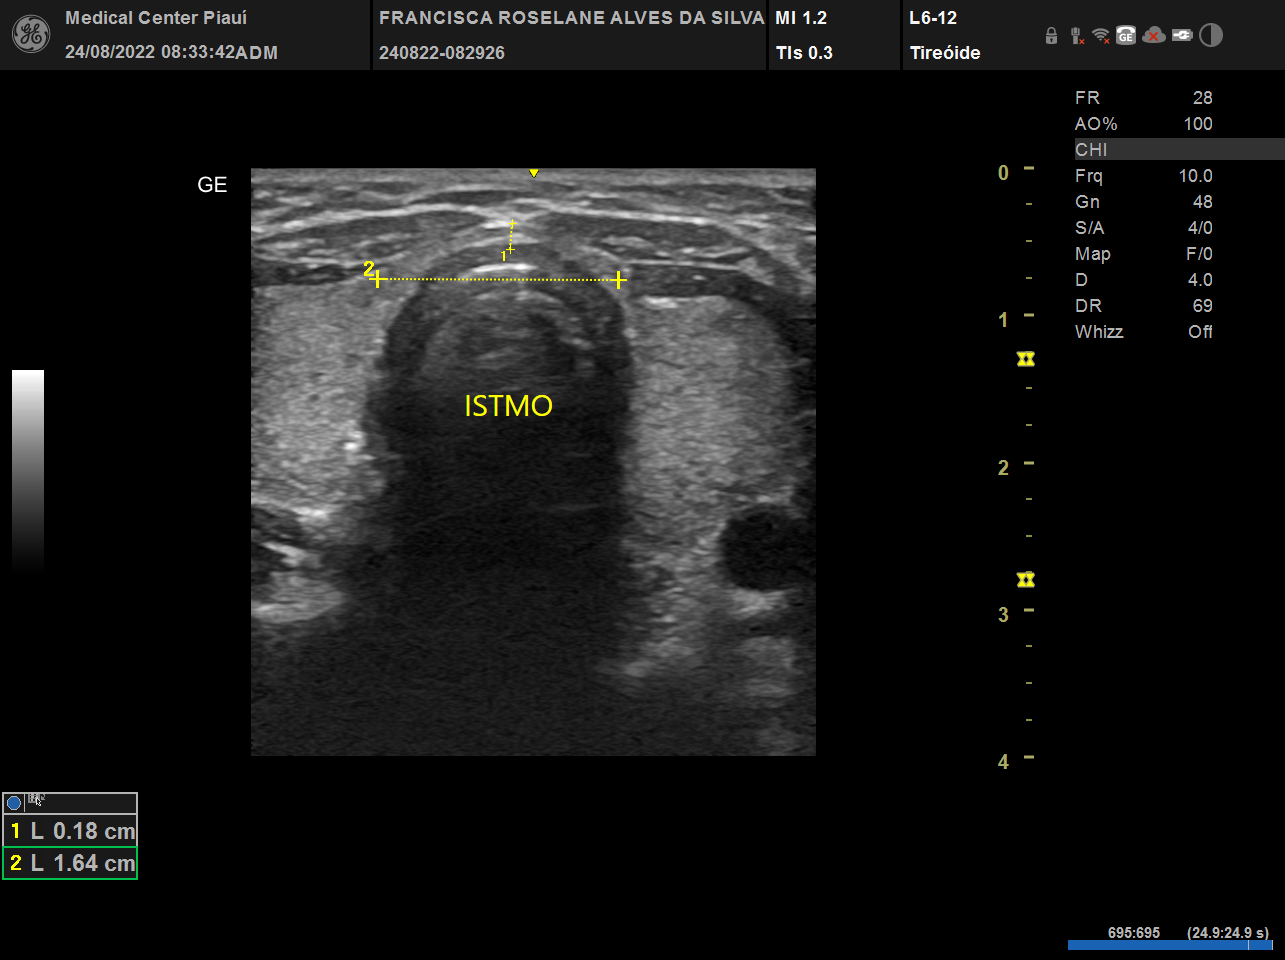

USG, TC e RN de tireoide